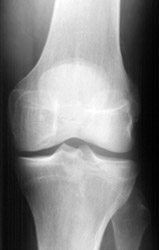

• Also known as "fender" or "bumper" fractures, tibial plateau fractures most often are the result of a moving vehicle striking the knee.

• Plateau fractures (medial and lateral) are the most common fracture sustained at the proximal tibia.

• When depression is not present, fracture may be difficult to recognize with standard radiographic exam. Alternative views and/or CT may be required for diagnosis.

• CT with multiplanar reconstruction (MPR) can be useful to help understand the anatomy of the fracture in 3D.

• Associated damage to the anterior cruciate ligament, medial collateral ligament and medial meniscus is common due to valgus stress placed on the knee during injury.

• Postraumatic arthritis and malunion can result.